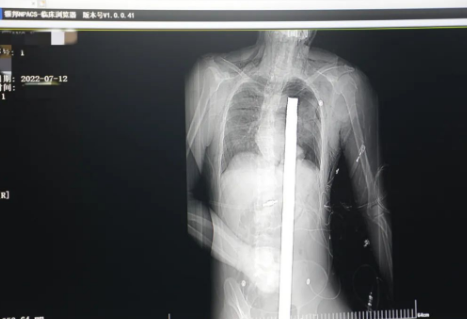

突發(fā)!太疼了,1.2米長的螺紋鋼從男子會(huì)陰部垂直穿入胸腔......7月12日下午16時(shí)10分,西安一處工地的一名26歲工友,不慎從10多米的高空墜落,不幸的是工地上一根直徑3厘米的螺紋鋼從男子會(huì)陰部垂直穿入體內(nèi),工地上的工友們小心翼翼地將連著的鋼筋截?cái)唷G闆r危急,立即送往西安國際醫(yī)學(xué)中心醫(yī)院急救中心,此時(shí)正是下午17時(shí)00分。

時(shí)間就是生命!此時(shí),西安國際醫(yī)學(xué)中心醫(yī)院展開了一場與生命賽跑的搶救,第一時(shí)間開辟綠色通道,急診X光片及CT顯示:異物經(jīng)會(huì)陰部貫穿盆腔、腹腔到達(dá)左側(cè)胸腔主動(dòng)脈弓水平。醫(yī)院創(chuàng)傷中心立即啟動(dòng)應(yīng)急預(yù)案,劉延彤副院長親臨指揮,下午17點(diǎn)48分,當(dāng)患者被送達(dá)手術(shù)室,胸外、心外、肝膽外科、胃腸外科,泌尿外科及麻醉科等多學(xué)科專家聯(lián)手對這名工友進(jìn)行“縱劈胸骨 前外側(cè)開胸探查 氣管及主支氣管修補(bǔ) 肺修補(bǔ) 血胸清除 開腹探查止血 腹膜后及盆腔探查......”手術(shù)。

情況緊急!術(shù)中探查后發(fā)現(xiàn),長120cm直徑3cm的螺紋鋼經(jīng)患者右側(cè)會(huì)陰部穿入,傷及直腸,途徑膀胱后方,左側(cè)髂總動(dòng)靜脈之間傷及左腎后,經(jīng)胰腺后方在肝脾之間穿破膈肌,在下肺靜脈前方穿入左肺穿破氣管及左右主支氣管膜部,止于主動(dòng)脈弓下水平,穿入體內(nèi)的部分達(dá)到75cm。